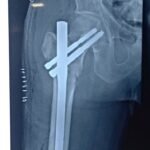

Complex trauma surgery is required for severe injuries such as multiple fractures, joint injuries, open fractures, or injuries involving previous implants or deformities. These cases need advanced surgical techniques, careful planning, and specialized orthopedic expertise. The aim of trauma and complex trauma surgery is to promote proper healing, restore movement, and help patients return to daily activities safely.